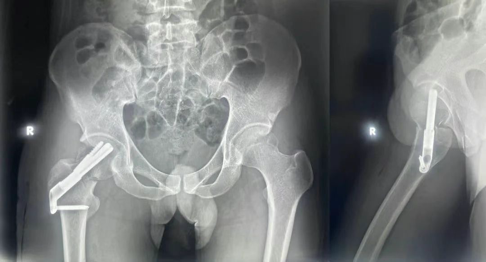

臨床上對(duì)于年輕患者或者骨骼質(zhì)量好的中老年患者,可使用3枚6.5mm或7.0mm或7.3mm的空心松質(zhì)骨螺釘固定。應(yīng)用導(dǎo)向器使3枚空心釘保持平行,以便于骨折滑動(dòng)加壓。在股骨頸內(nèi),螺釘應(yīng)該沿邊緣擰入,注意螺釘?shù)穆菁y都要進(jìn)入股骨頭而不應(yīng)該跨越骨折線,只有這樣才能獲得骨折端間加壓。術(shù)中螺釘都要擰緊并反復(fù)確認(rèn)。如使用牽引床,必須放松牽引??招穆葆斠部梢越?jīng)皮置入。必須作正位、側(cè)位及45°斜位透視,以確保螺釘不會(huì)穿透髖關(guān)節(jié)。1、具體手術(shù)操作技術(shù):以臨床上普遍應(yīng)用的“倒三角”置釘為例:首先在透視下,使用X線在兩個(gè)平面透視確定中下部導(dǎo)針布局。做一個(gè)可向近端延伸2-3cm的皮膚切口。沿切口分離筋膜層,使用Cobb分離器沿股外側(cè)肌縱行纖維分離。將導(dǎo)針放置于兩個(gè)平面都完美的位置。沿股骨頸前方放置1枚導(dǎo)針有助手確定前傾角。第1枚導(dǎo)針固定后,使用平行導(dǎo)向器確定后上和前上導(dǎo)針獲得股骨頸內(nèi)后方和前方皮質(zhì)支撐。具體方法是于小轉(zhuǎn)子之上沿股骨頸遠(yuǎn)端皮質(zhì)經(jīng)股骨距置入一枚導(dǎo)針;接著以平行的方式置入近端的2枚導(dǎo)針,其位置應(yīng)盡可能靠上,且距前后皮質(zhì)5mm;然后調(diào)整導(dǎo)針進(jìn)入的深度,使其深達(dá)軟骨下5mm處;最后擴(kuò)孔、測(cè)深、擰入加壓空心螺釘。確定不要低于小粗隆進(jìn)針,沿著股骨距向近端走行。使螺紋導(dǎo)針位于關(guān)節(jié)面面下方。勿使導(dǎo)針穿破關(guān)節(jié)面。確定合適的螺釘長度,測(cè)量導(dǎo)針長度后誠去5mm。通常使用自攻自鉆螺釘,但有時(shí)對(duì)骨質(zhì)厚的忠者需要在外側(cè)皮質(zhì)預(yù)鉆孔。如果空間允許,可使用墊片。對(duì)手后方嚴(yán)重的粉碎性骨折的忠者,可能有必要使用第4枚螺釘(菱形排列)。2、注意事項(xiàng):放置導(dǎo)針時(shí)必須特別小心,因?yàn)椴磺‘?dāng)?shù)膶?dǎo)針通道(多種嘗試或試圖在小轉(zhuǎn)子下方進(jìn)針)可能會(huì)造成股骨粗隆下骨折。生物力學(xué)模型證明,螺釘?shù)奈恢脮?huì)影響股骨粗隆下骨折的發(fā)生。股骨頸骨折的模型使用遠(yuǎn)頂端螺釘或近頂端螺釘配置固定。遠(yuǎn)頂端配置比近頂端配置可展現(xiàn)出更強(qiáng)的負(fù)荷(在股骨粗隆下骨折出現(xiàn)之前)。最近也有臨床研究報(bào)道了粗隆下骨折和不愈合率升高的問題。盡可能使用墊片,墊片的應(yīng)用可能能增加壓力??招尼敼潭ㄖ荒茉讷@得滿意復(fù)位的情況下再置入。盡管目前空心螺釘治療股骨頸骨折已經(jīng)非常普遍,但在手術(shù)置入空心螺釘?shù)臄?shù)量以及構(gòu)型等方面仍存在不同意見,通常取決于術(shù)者的偏好;同時(shí)患者的骨密度、螺釘強(qiáng)度、治療成功與否等因素也對(duì)其有所影響。1、空心螺釘?shù)臄?shù)目:股骨頸骨折一般采用2-4枚空心螺釘進(jìn)行固定。多數(shù)情況下采用3枚,因其可承受較強(qiáng)的前方應(yīng)力,增加了穩(wěn)定性,能減少骨折斷端移位。對(duì)于Pauwells角>50°的股骨頸骨折,采用2枚更為合理。而伴有股骨頸后方嚴(yán)重粉碎性骨折的患者,有學(xué)者主張采用4枚空心螺釘。但是,目前比較主流的做法仍是采用3根空心螺釘進(jìn)行固定。2、空心螺釘?shù)臉?gòu)型:采用3枚空心螺釘進(jìn)行股骨頸骨折內(nèi)固定時(shí),一般認(rèn)為應(yīng)遵循“滑動(dòng)加壓”的理論,使植入的3枚螺釘正位片上彼此平行、側(cè)位片上呈現(xiàn)三角形構(gòu)型。采用這種方式時(shí),3枚平行的空心螺釘既可提供很好的力學(xué)支撐,又可形成可滑動(dòng)式軌道,在髖部肌群的收縮作用下,骨折塊可沿股骨頸軸線方向滑動(dòng),在骨折斷端形成壓力,促進(jìn)骨折愈合。但3枚空心螺釘是以正三角構(gòu)型還是倒三角構(gòu)型布局一直存在爭議。許多研究證實(shí),相比于正三角構(gòu)型,倒三角構(gòu)型能提供更好的機(jī)械穩(wěn)定性,其原理為:在倒三角構(gòu)型中,3根空心螺釘盡量垂直于骨折線置入,使斷端軸向加壓,對(duì)抗強(qiáng)大的剪切力;遠(yuǎn)端為1枚螺釘,沿股骨頸遠(yuǎn)端皮質(zhì)經(jīng)股骨矩置入,尖端深達(dá)于軟骨下5mm左右,可確保固定的牢固性;近端為另外2枚螺釘,分別平行于第1枚由股骨頸前后側(cè)皮質(zhì)置入,因?yàn)楣晒穷^中央和上方骨小梁較下方更密集,把持效果更好,所以這2枚空心螺釘位于上方,能比正三角構(gòu)型提供更好的把持力以及抗拉力作用。近年來,F(xiàn)ilipov提出了一種新的空心螺釘內(nèi)固定置釘方法——“強(qiáng)斜”置釘(“F”形置釘技術(shù))。該方法通過2枚以不同傾斜度、不同平面經(jīng)股骨距置入的空心螺釘來提供良好的皮質(zhì)支撐力和縱向穩(wěn)定性,另外1枚位于近端,平行于近端皮質(zhì)置入,用以提供抗拉力作用,防止骨折端分離。研究證實(shí),相比于普通螺釘植入方式,這種置釘方式能在患者活動(dòng)時(shí)提供持續(xù)穩(wěn)定性,且骨折越不穩(wěn)定,其優(yōu)勢(shì)越明顯。